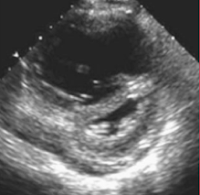

- RV dilatation with a RV end-diastolic/ LV end-diastolic Ratio > 0.9 on the apical 4 chamber view (4; 7)

RV Dilation